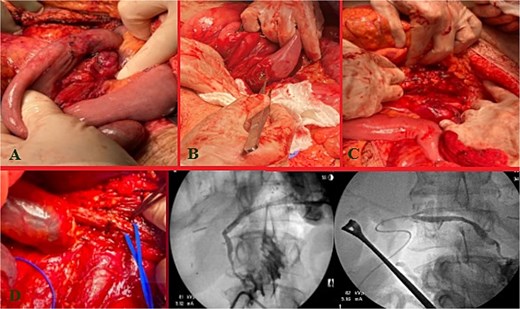

The patient stayed a total of 77 days at the hospital with around 54 days spent in the ICU. He was initially in ICU care for his extensive traumatic and complicated recovery. On POD1–3 increased bilious output was noted from a JP drain. He was taken back to the operating room (OR) on POD3 for re-exploration. There was a small contained biliary collection of ~2.23 cm in the GB fossa without active bile leak noted, viable bowel, and intact duodenal repair. The patient underwent placement of a gastrostomy and feeding jejunostomy tubes, an appendectomy, and abdominal wall reconstruction with Ovitex. He returned to the OR on POD7 for frank blood noted in another JP drain where a persistent gush of blood was noted at the GB fossa. This was repaired with multiple clips and figure of 8 sutures. The abdomen was packed and the Abthera wound vac was replaced. Repeat re-exploration on POD8 noted continued hemostasis, but there remained bile near the porta hepatis and two additional JP drains were left in the region of concern. He recovered well for the consequent days with stabilized bilirubin levels (Fig. 2A). However, on POD20, it was noted that he had increasing bile output of over 1 L over 24 hours. The bile was consequently fed back through his J-tube, and on POD25, a hepatobiliary iminodiacetic acid scan (HIDA) scan failed to demonstrate the leak and an initial ERCP attempt failed secondary to a duodenal diverticula. On POD27, magnetic resonance cholangiopancreatography (MRCP) demonstrated a common hepatic duct stricture. ERCP was successful in cannulation of the ampulla on POD32 with continued lack of contrast extravasation at the distal common bile duct. On POD35, percutaneous transhepatic cholangiography drain was placed to relieve concerns of a leak. On POD54, interventional radiology and gastroenterology successfully completed a ERCP rendezvous procedure to place a biliary stent over the area of stricture. (Fig. 2B) This intervention successfully reduced the amount of bilious and overall JP output. On hospital Day 77, he was consequently discharged with all drains removed and tolerating a regular diet.

Injury sequelae and interventions. A: Re-exploration due to bilious changes. B: Delayed presentation of common hepatic duct stricture with rendezvous procedure.